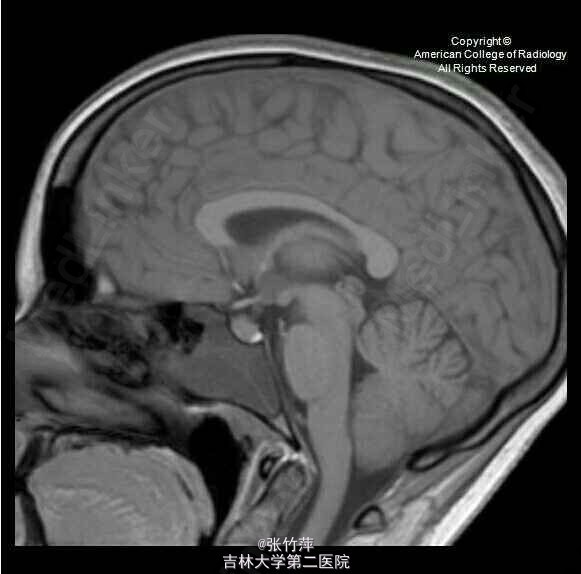

女,20岁。头痛一月余,伴复视,流泪,视力下降。

脑部磁共振图片如下

蝶窦粘液囊肿